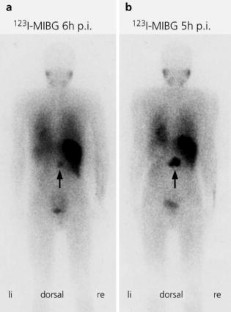

Paradoxe Nuklidspeicherung eines onkozytären Nebennierenrindenkarzinoms

123I-Metaiodobenzylguanidine- (MIBG-) scintigraphy: paradoxical positivity in an oncocytic adrenocortical carcinoma

Das mit Radiojod markierte Katecholaminanalogon Methyljodbenzylguanidin (MIBG) eignet sich aufgrund seiner selektiven Aufnahme in chromaffine Gewebe in hervorragender Weise für die bildgebende Diagnostik des Phäochromozytoms und besitzt hier nach Literaturangaben eine Sensitivität von etwa 90% und eine Spezifität von annähernd 100%. Die falsch-positive oder paradoxe MIBG-Speicherung einer adrenokortikalen Neoplasie stellt demgegenüber eine Rarität dar. Wir berichten über diese Situation am Beispiel eines metastasierten onkozytären Nebennierenrindenkarzinoms mit teilweise therapeutisch genutzter MIBG-Speicherung in verschiedenen Tumormanifestationen.

123I-metaiodobenzylguanidine (MIBG), a radio-labeled catecholamine analogue, is used for the imaging of pheochromocytoma based on the selective uptake of MIBG by chromaffin tissues. MIBG scintigraphy displays high sensitivity (90%) and specificity (close to 100%). In contrast, the false-positive uptake of MIBG by adrenal cortical carcinoma is rare. Here, we report a metastatic oncocytic adrenal cortical carcinoma with MIBG uptake used for therapeutic purposes.